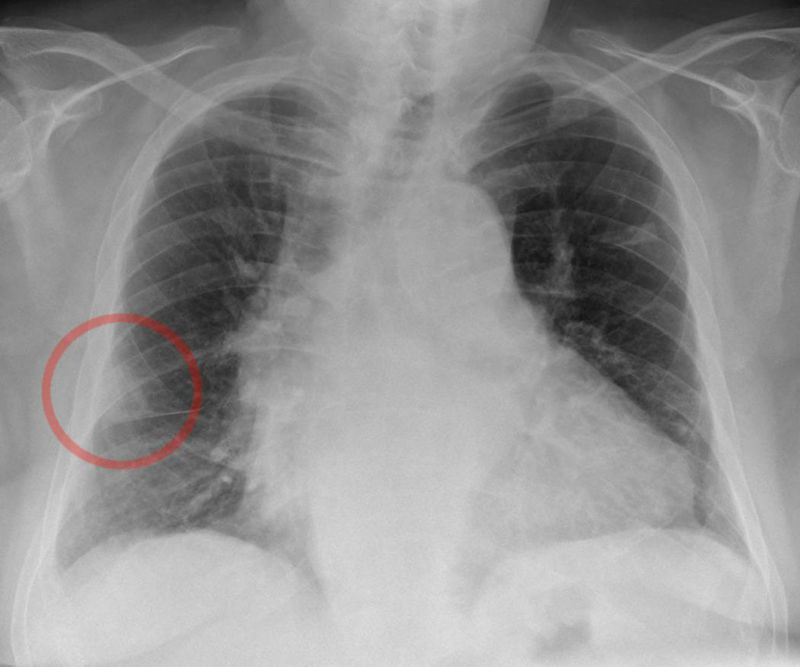

Pulmonary embolism

Hampton's Hump